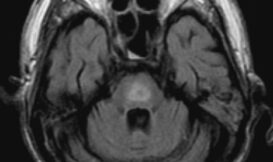

細胞內的滲透壓,也就是水和溶質的比例得維持穩定,才不會發生細胞內太多水脹破細胞,或是細胞脫水的狀況。一般來說,我們體內的細胞有一套很好的滲透壓平衡機制,但當細胞面對快速的滲透壓變化,特別脆弱的腦細胞可真的真的受不了......